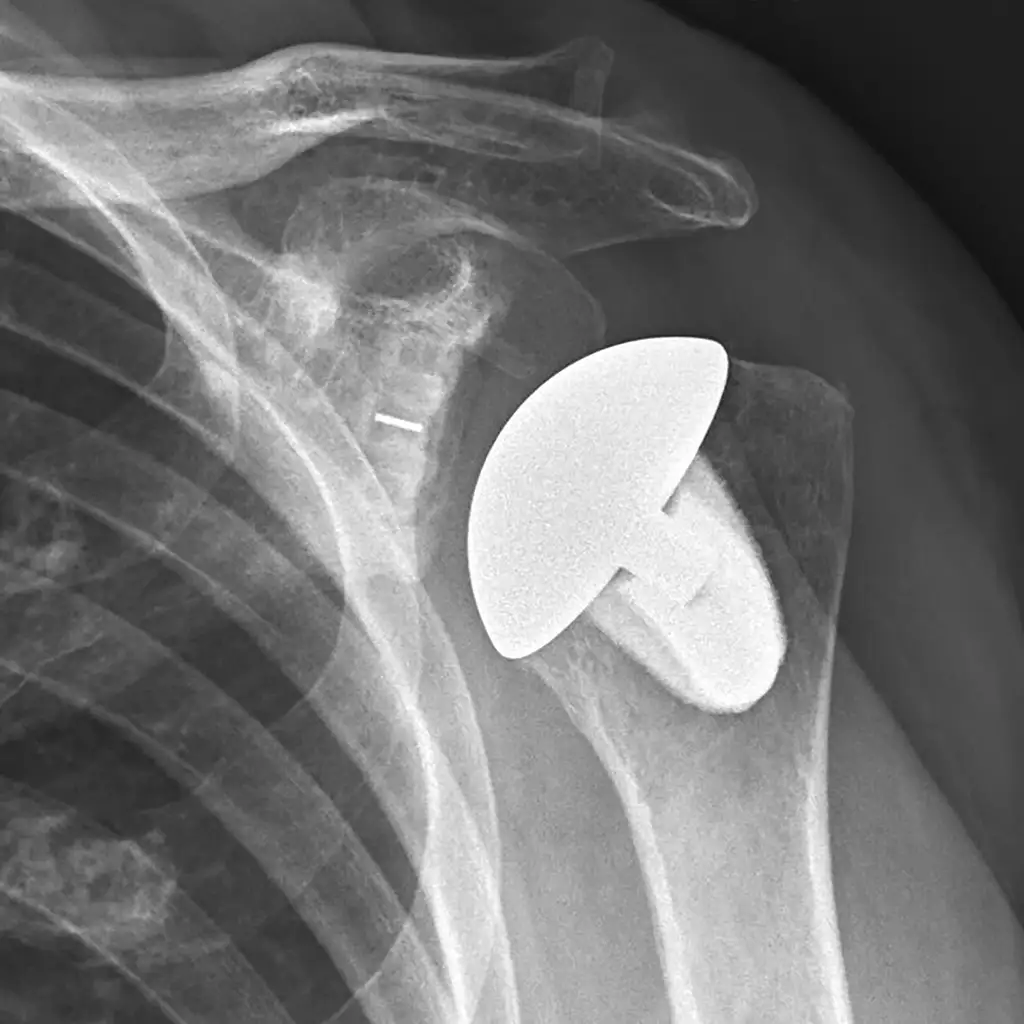

Total Shoulder Replacement

Total shoulder replacement can relieve severe shoulder pain and restore mobility when arthritis or joint damage hasn’t improved with other treatments. The procedure replaces the worn joint surfaces, helping you return to more comfortable daily movement.